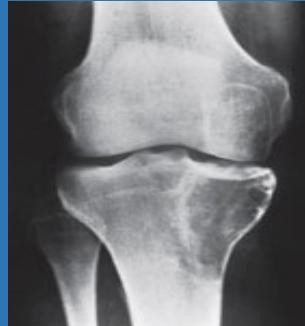

Case 4: Aggressive Bone Tumor (18 years old)

Clinical Presentation

- Painful mass at right femur

- Limited knee joint motion

- History of trauma 8 weeks prior (simple fall at home)

- Initially diagnosed as simple contusion by primary care physician

Radiographic Findings

- Radiolucency and sclerosis

- Poorly defined margins

- Extension into soft tissue

- Periosteal reaction:

- Sunburst (sun-ray) appearance

- Codman’s triangle

Diagnosis: Osteosarcoma

Staging Investigations

- CT chest:

- Mandatory staging study

- Evaluates for pulmonary metastasis

- MRI:

- Very informative, must include entire involved bone

- Determines soft tissue and marrow involvement

- Bone scan:

- Mandatory imaging study to discover skip lesions

- Always shows increased uptake

Treatment Protocol

- Metastasis workup:

- Well-planned incision for biopsy

- Neoadjuvant chemotherapy

- Surgical management:

- Wide resection

- Custom-made prosthesis reconstruction

- Adjuvant chemotherapy